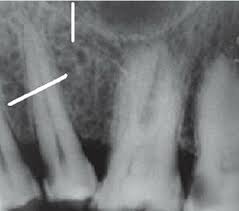

alveolar crest

coronal-most portion of the alveolar process

in health, located 1 to 2 mm apical to CEJ

The height of the Alveolar Crest is in health

1-2mm apical to CEJ

WHY there’s 1-2mm between CEJ and alveolar bone; 1-2mm represents supra-crestal tissue attachment (STA) or biologic width, and supra-crestal attached tissue (SAT)